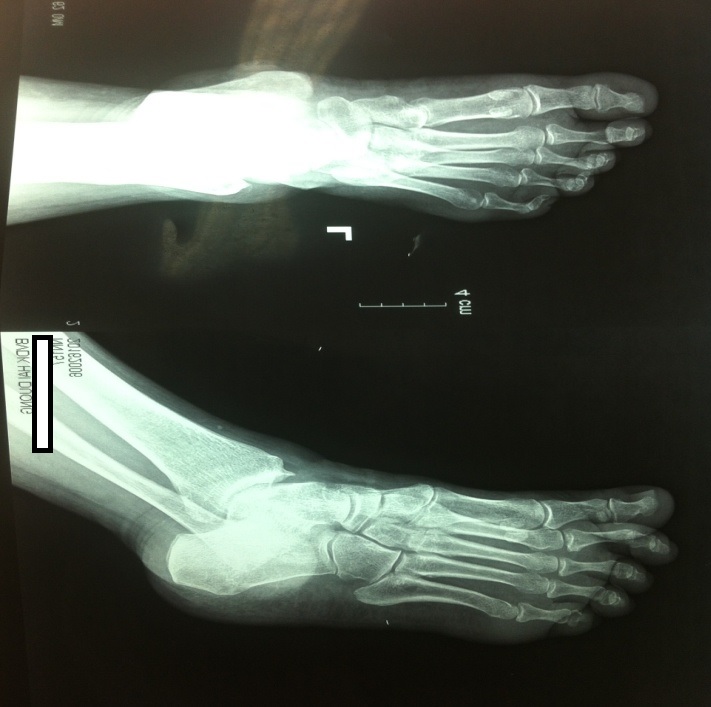

7. Chụp x quang xương bàn chân và lồng ngực: không thấy tổn thương.